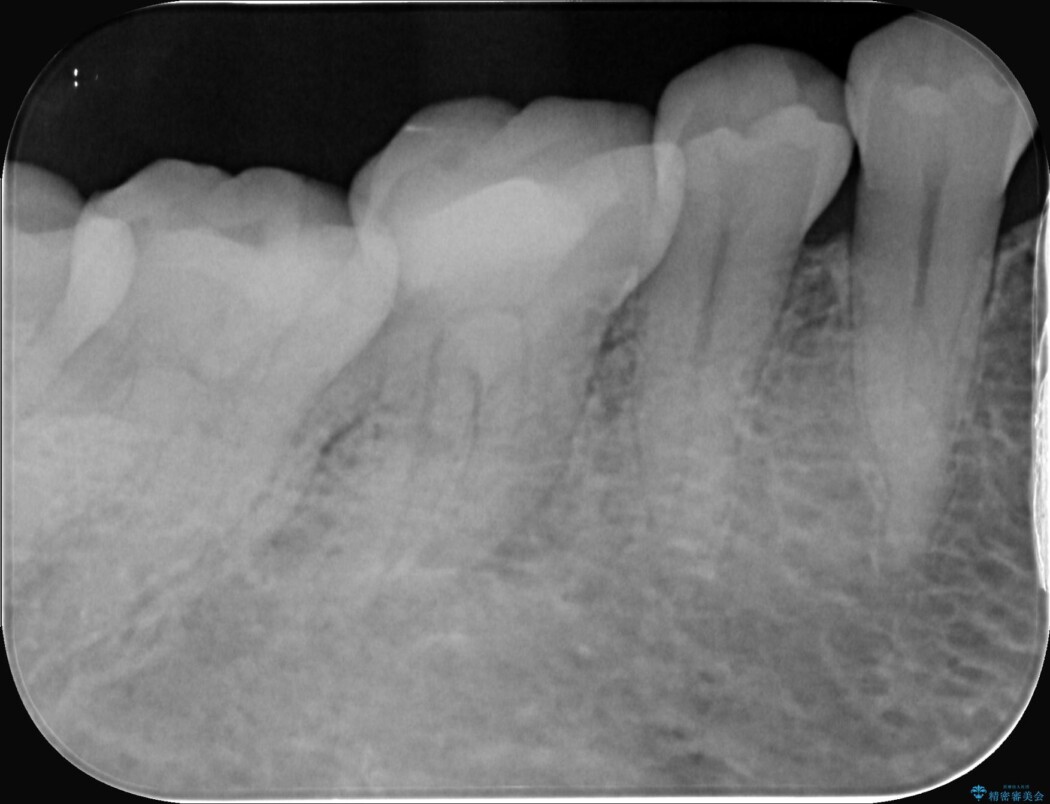

精密検査の結果、根の先に大きな病変が認められますが、根管内が狭窄し湾曲しているため、非常に難易度の高いケースです。

通常の治療器具では奥まで届かず、そのままでは再発や抜歯になるリスクが高いため、マイクロスコープを使用して根の奥まで精密に清掃・殺菌し、歯を残すための治療計画を立てました。

術後の経過は非常に良く、あんなに大きかった膿の袋は消え、健康な骨が再生しているのが確認できました。痛みや腫れも消えて抜歯を免れ、現在は被せ物を入れてしっかりお食事を楽しんでいただけるようになっています。